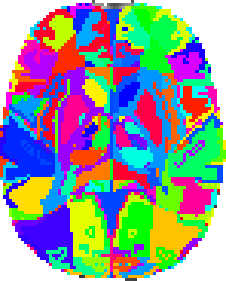

Harvard-Oxford cortical and subcortical structural atlases

Probabilistic atlases covering 48 cortical and 21 subcortical structural areas, derived from structural data and segmentations kindly provided by the Harvard Center for Morphometric Analysis.

Probabilistic atlases covering 48 cortical and 21 subcortical structural areas, derived from structural data and segmentations kindly provided by the Harvard Center for Morphometric Analysis.

T1-weighted images of 21 healthy male and 16 healthy female subjects (ages 18-50) were individually segmented by the CMA using semi-automated tools developed in-house. The T1-weighted images were affine-registered to MNI152 space using FLIRT (FSL), and the transforms then applied to the individual labels. Finally, these were combined across subjects to form population probability maps for each label.